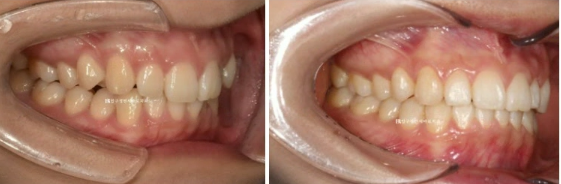

송곳니 덧니 등 앞니를 가지런하게 만들고 싶어 내원하신 분 입니다.

23.10

결혼을 앞두고 계셔서 전체교정은 부담스럽다 하셨고 최소한의 개입만으로 단기교정치료를 원하셨습니다.

다행히 어금니 교합이 양호한 편이고 앞니 부분교정도 권유드렸습니다.

파란 화살표는 왜소치이고 앞니를 제외한 뒤쪽 어금니 배열은 양호합니다.

파란 화살표는 왜소치입니다.

덧니나 왜소치가 있는 경우라면 앞니 중심선이 그쪽으로 쏠려있는 경우가 많습니다.

우측 사진에서 첫번째 작은어금니 교합이 떠 있는 것이 보입니다.

통상 앞니 부분교정은 송곳니에서 송곳니까지 6개 앞니만을 대상으로 하지만, 작은 어금니 교합도 개선하기 위해서

송곳니 뒤쪽 1개씩 총 8개 치아에 장치를 붙이기로 했습니다.